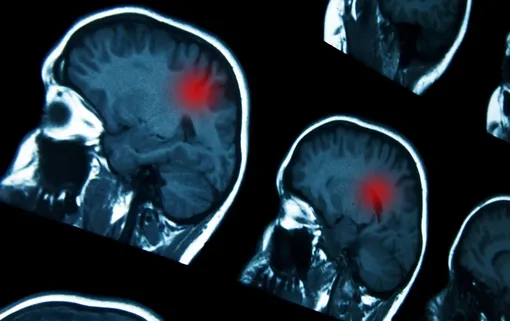

Новая работа ученых позволяет медикам прогнозировать риск поражения мозга. Если у раковой клетки выявлены нарушения в 17-й хромосоме, пациент будет получать более интенсивную терапию и проходить регулярную МРТ-диагностику для раннего обнаружения метастазов. Это значительно повышает шансы на успешное лечение и сохранение жизни.